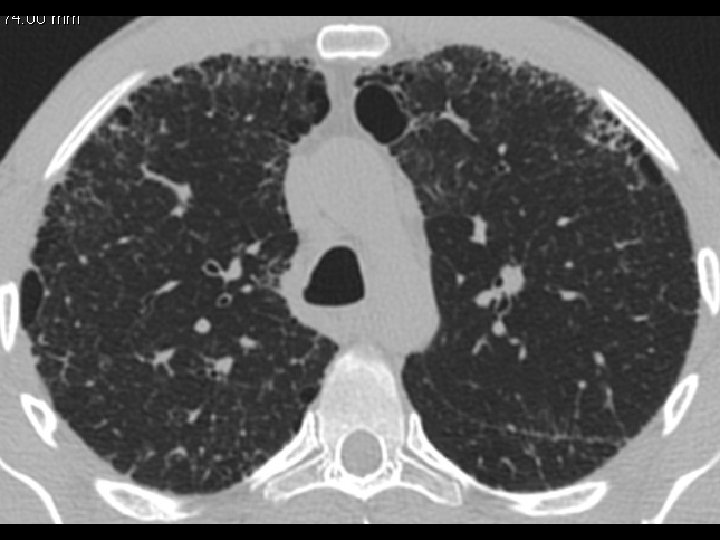

High-resolution CT scan

Subpleural, basal predominance Reticular abnormality Honeycombing with traction bronchiectasis UIPUIP Pattern

Subpleural, basal predominance Reticular abnormality Honeycombing with traction bronchiectasis Profuse micronodules UIPUIP Pattern Inconsistent with UIP Pattern